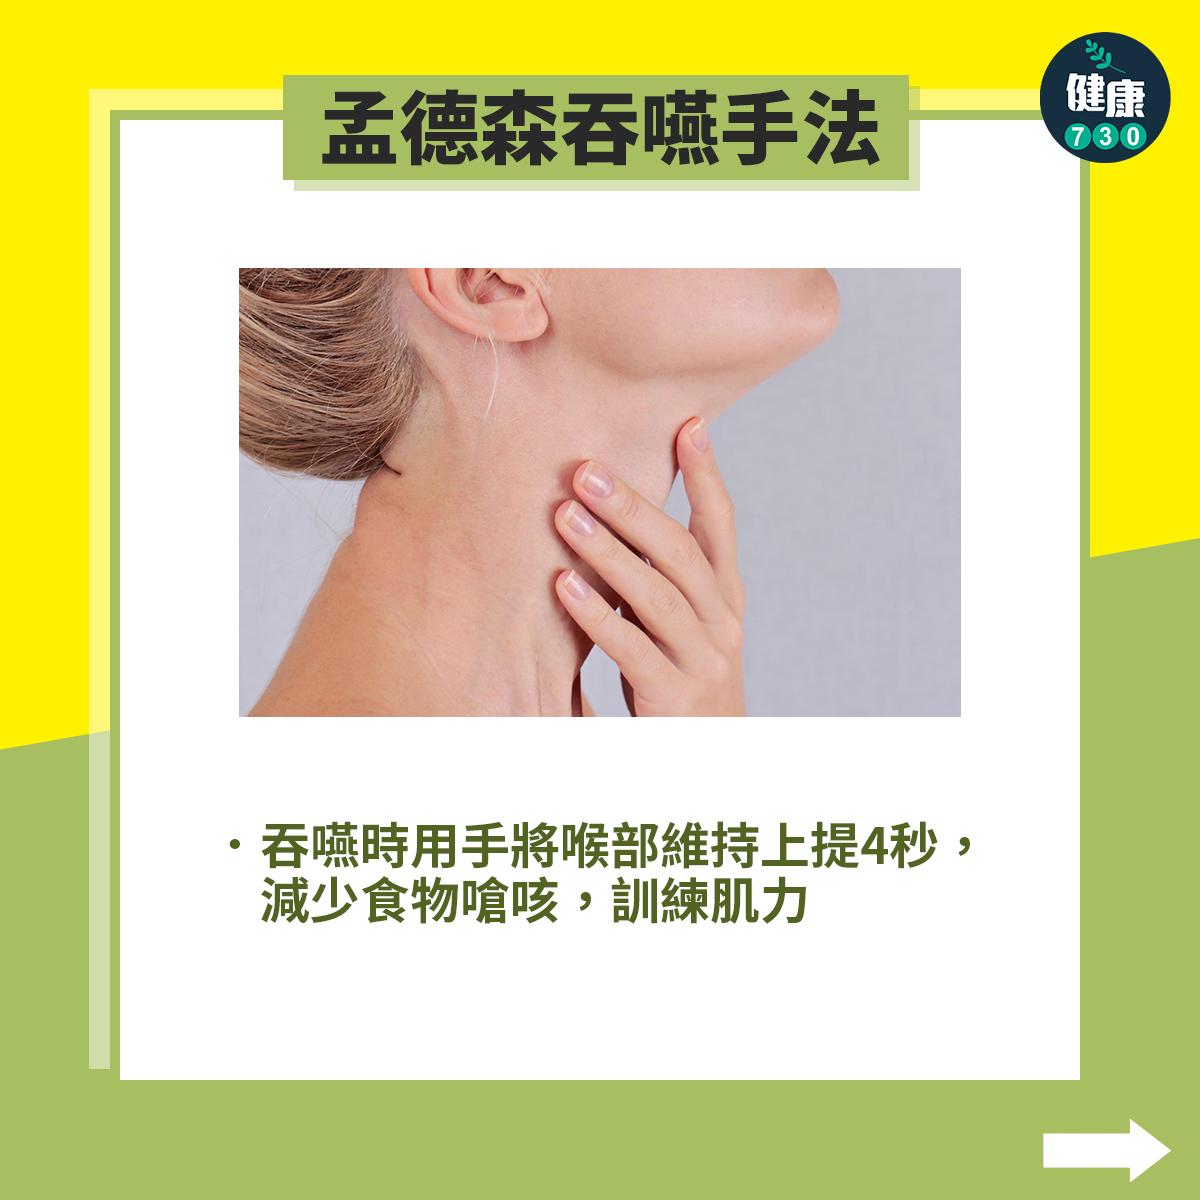

中風復健|5招改善中風後吞嚥困難